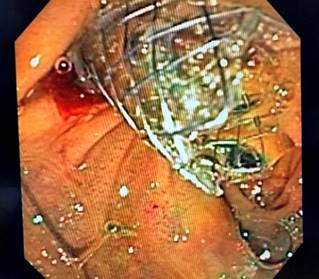

Con los hallazgos descritos se decidió el manejo paliativo y se llevó a CPRE con la intención de realizar una derivación biliar con stent; se encontró la papila distorsionada con retracción local de las paredes duodenales y se logró la canulación de la vía biliar distal, pero fue fallida para la vía biliar proximal. Entonces, se realizó la derivación biliodigestiva guiada por USE, en la que se encontró una infiltración neoplásica de la papila duodenal que impide su canulación y la cabeza del páncreas tenía una lesión hipoecoica heterogénea de 23 mm de diámetro con una dilatación retrógrada de la vía biliar hasta 18 mm (Figura 4). Se realizó una punción inicial de la masa para el estudio histológico y, posteriormente, de la vía biliar transduodenal con una aguja de 19 Fr, avanzando la guía hidrofílica 0,035; la dilatación se realizó con un balón dilatador biliar bajo control fluoroscópico y la posterior colocación del stent biliar metálico completamente cubierto de 10 x 80 mm, el cual se liberó bajo control endoscópico y fluoroscópico con una adecuada apertura y drenaje del medio de contraste y de bilis clara, sin complicaciones posteriores (Figuras 5 y 6). El reporte de la citología obtenida por endosonografía confirmó el compromiso por adenocarcinoma. A los 2 meses se le realizó control de bilirrubina total en 2,42 mg/dL; directa, en 1,85 mg/dL; e indirecta, en 0,58 mg/dL (Figura 7). La paciente continuó el manejo con oncología y cuidados paliativos.